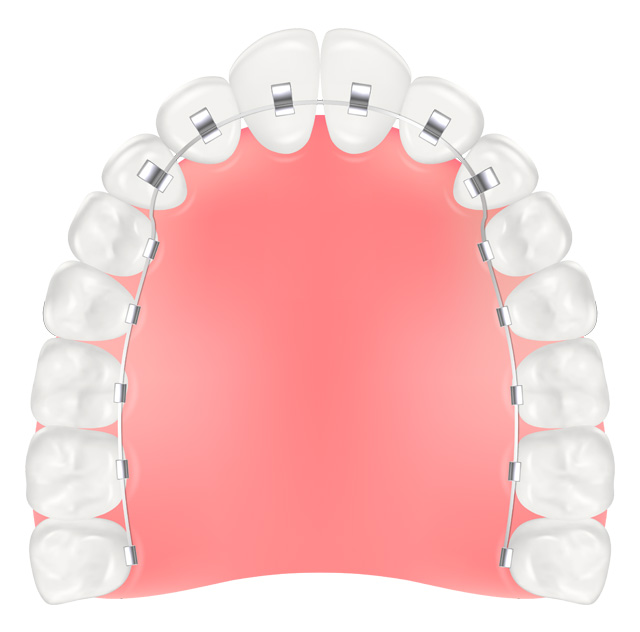

リンガルブラケット(裏側矯正)

歯の裏側に装着するため装置が目立ちにくく、成人矯正の需要が高まるにつれて選ばれることが増えています。表側のブラケットより価格は比較的高く、調整に時間がかかります。